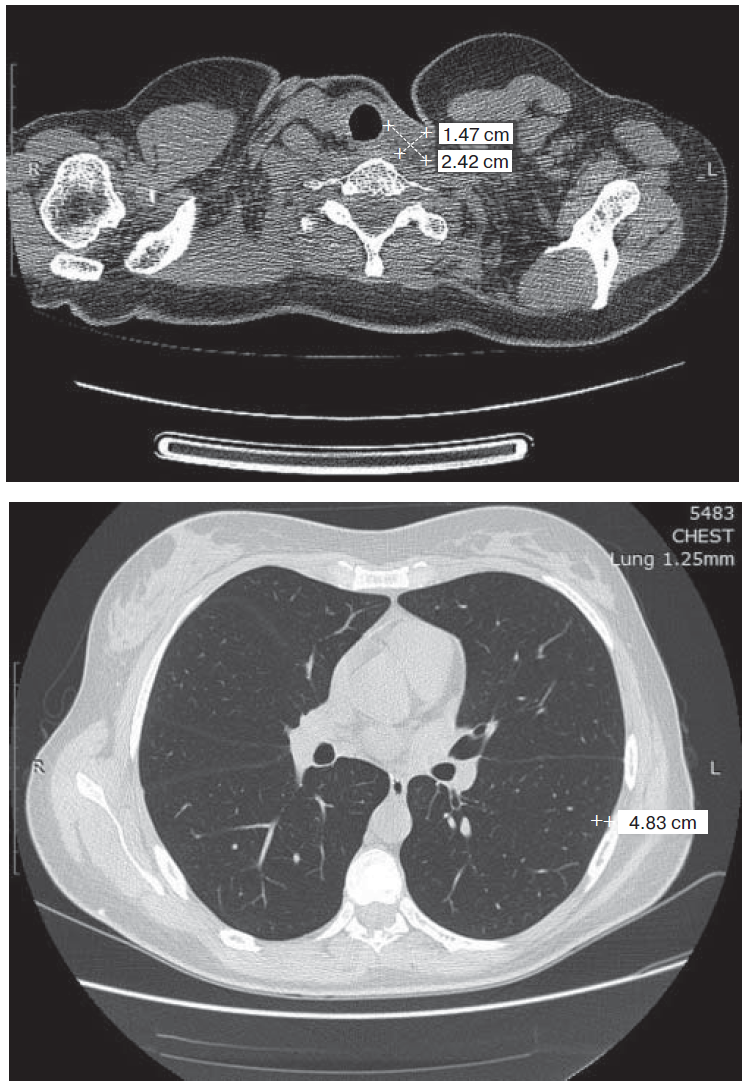

3. Fig. 2. Computer tomography of thoracic organs cavities: tumor formation in S6 of the left lung 5 × 4 mm in size.

View (451KB)

7. Fig. 6. Computer tomogram of thoracic organs cavity: soft tissue formation in the left tracheo- esophageal groove at Th1-Th2 level 16 × 13 mm.

View (362KB)